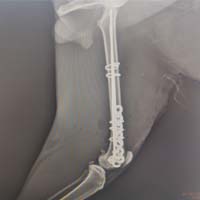

Yalıkavak veteriner kliniğimizde gerçekleştirdiğimiz ortopedik cerrahi uygulamalar:

Ortopedik cerrahi oldukça titizlik ve özen gerektiren cerrahi uygulamalardır. Diğer cerrahi disiplinlere nazaran asepsi ve antisepsi (sterilizasyon) konusunda ASLA hata kabul etmez. Eğer bu aşamada özensiz davranılırsa, postoperatif süreçte kemik dokunun iltihaplanmasına neden olup, kemiklerin kaynaması gecikmiş olur.